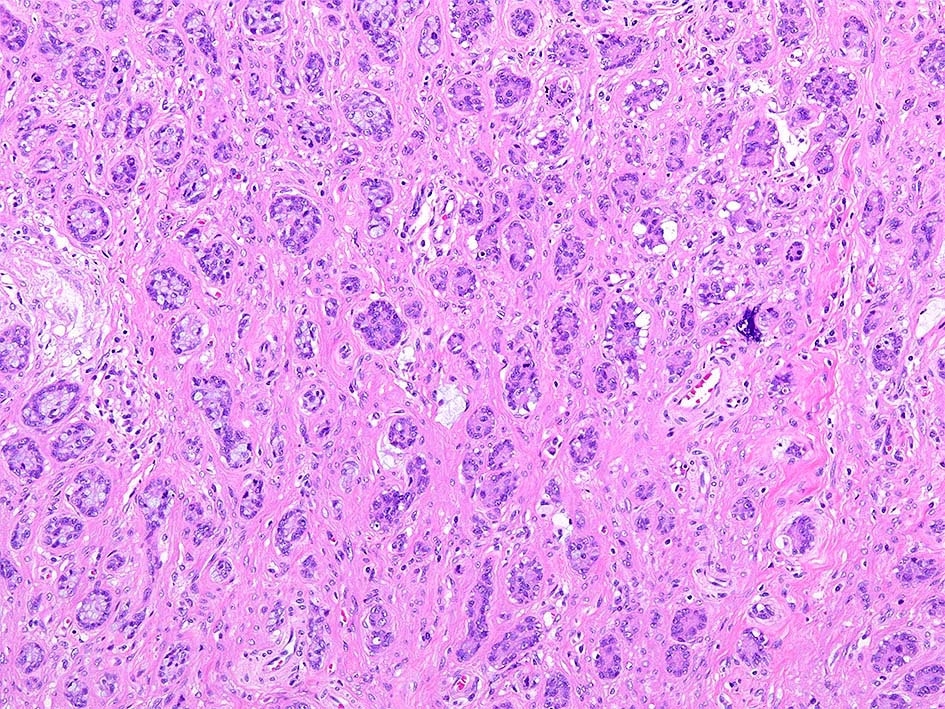

Goblet cell carcinoid tumor of the appendix

31歳 女性 X年4月下腹部痛で虫垂炎と診断され保存的治療をおこなう. 同年 7月手術を希望し腹腔鏡下虫垂切除術が施行される.

組織所見